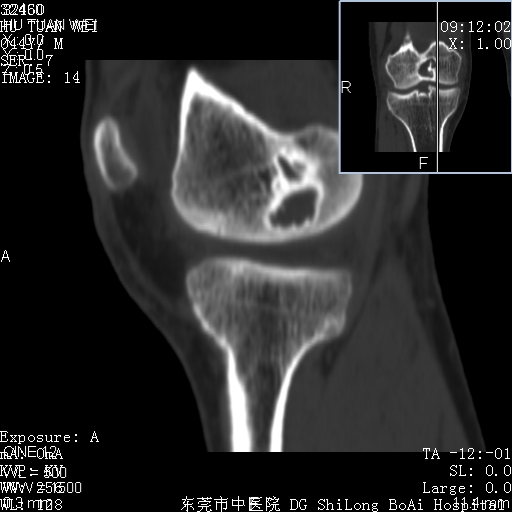

中年男性,膝韧带损伤术前检查!其他病史不清粗,不是我接手病人、且出院了!

1、股骨下段囊状膨胀性病变,边缘硬化明显,内多个残留骨棘呈多房型改变,囊腔密度较高无钙化,膝关节滑膜囊增厚,密度增高,关节腔少量积液。考虑:邻关节囊肿、退变性囊肿(软骨下囊肿)、着色性绒毛结节性滑膜炎、abc、骨巨、良性纤维组织细胞瘤等鉴。虽然年龄偏大,部位于骨端,但有外伤史,本人还是倾向于动脉瘤样骨囊肿(abc)可能性大。邻关节囊肿及软骨下囊肿次之考虑。

2、胫骨髁间棘撕脱骨折,交叉韧带损伤可能;

3、关节退行性改变。

病理结果:色素沉着绒毛结节性滑膜炎

感谢反馈病理结果!本病为慢性关节病变。以关节滑膜高度增生、绒毛结节形成伴含铁血黄素趁着为特点。病因:有炎症、肿瘤、外伤关节出血、代谢障碍、变态反应及感染等学说。增强扫描呈关节腔内单个或多个强化的软组织结节影或滑膜不规则增厚伴关节积液为本病的特征性表现。